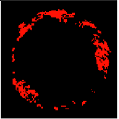

Since clustering algorithms will not return the same cluster index value every time, the colour of each cluster should be determined. With respect to the colour of each cluster, its matching plaque components can be determined as NC: red, DC: white, FI: dark green, and FF: light green [45].

Class label of each colour feature should be determined to perform the pixel wise classification [73]. The non-zero pixels in DC, NC, FF, and FI images were saved into CF matrix. Their corresponding labels were calculated and saved into the vector L [45].

Four colour images representing the plaque components are provided using the assigned label during the pixel classification process. The area of each plaque component can be calculated based on the number of non-zero pixels in each image. The area of NC, DC, FF, and FI images can be represented as tissue area features of fNC, fDC, fNC, fFF, and fFI, respectively. These values are considered to be the primary features for TCFA detection.